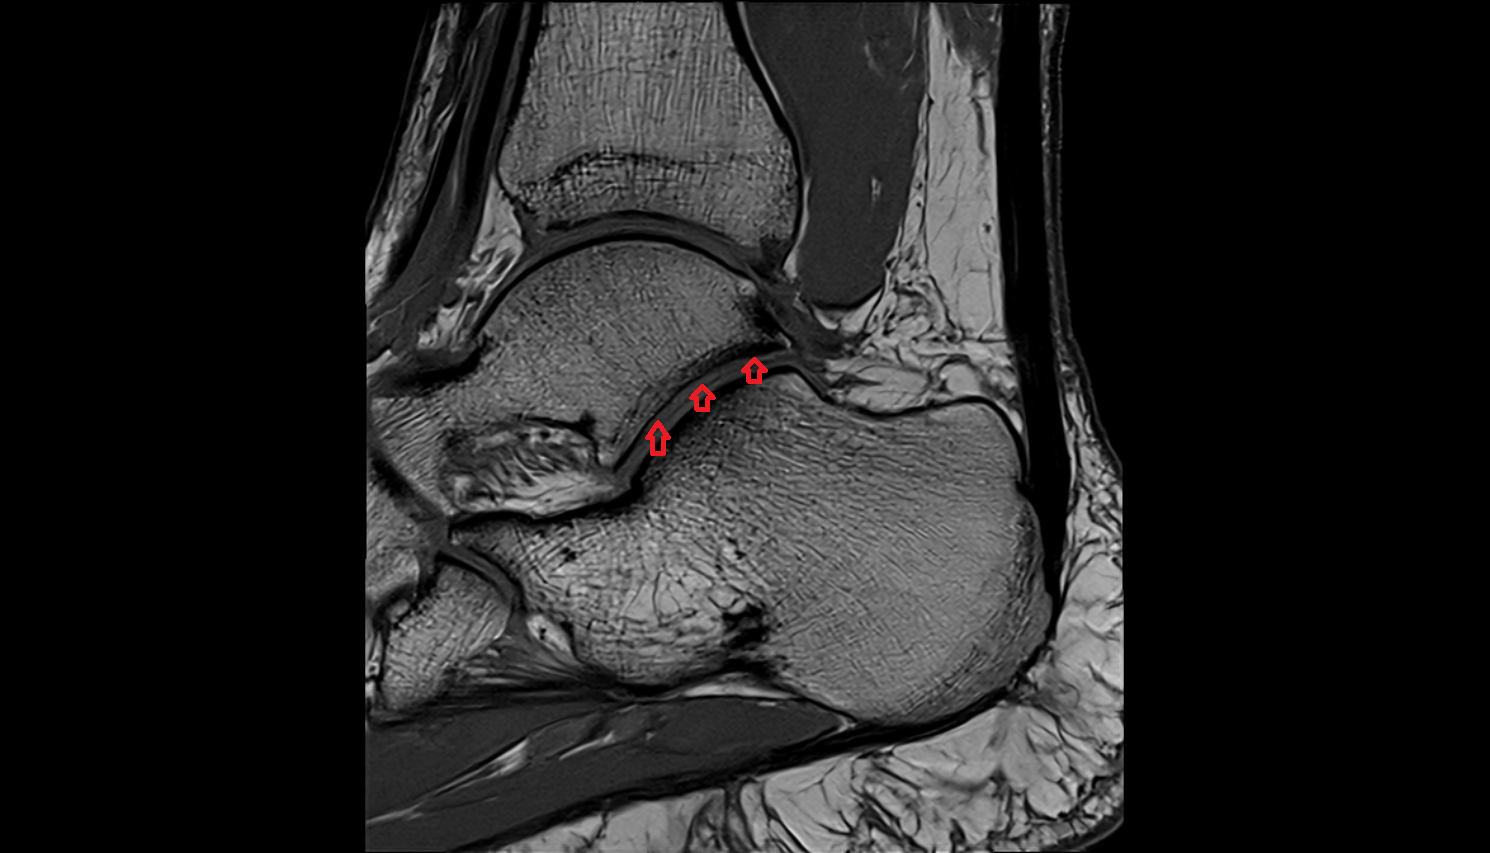

- Achilles tendon

- Anterior talofibular ligament

- Posterior talofibular ligament

- Anterior inferior tibiofibular ligament

- Posterior inferior tibiofibular ligament

- Deltoid ligament complex

- Talocalcaneal interosseous ligament

- Kager fat pad (pre-Achilles fat pad)